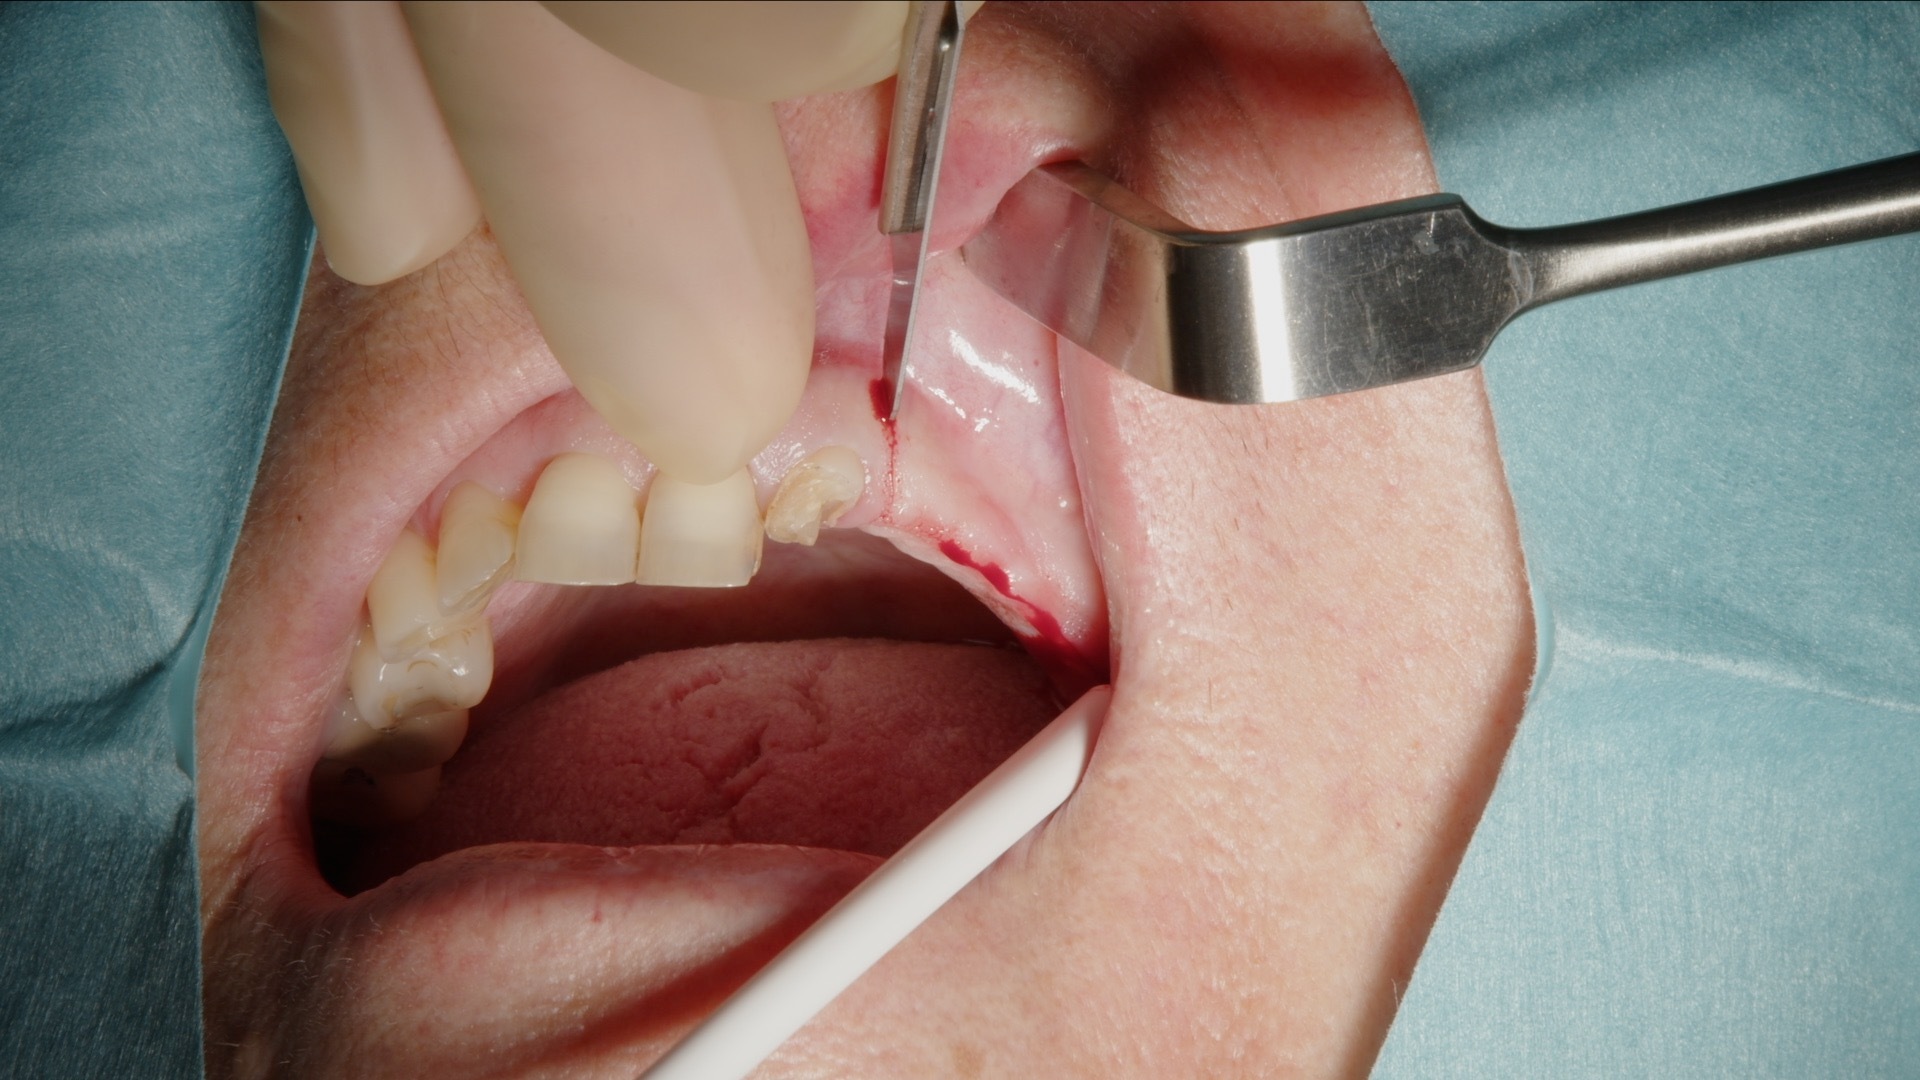

1. Incision och lambåpreparation inför skapande av lateralt fönster.

2. Preparering av lateralt fönster med Acteon Piezo Cube och diamantspets.